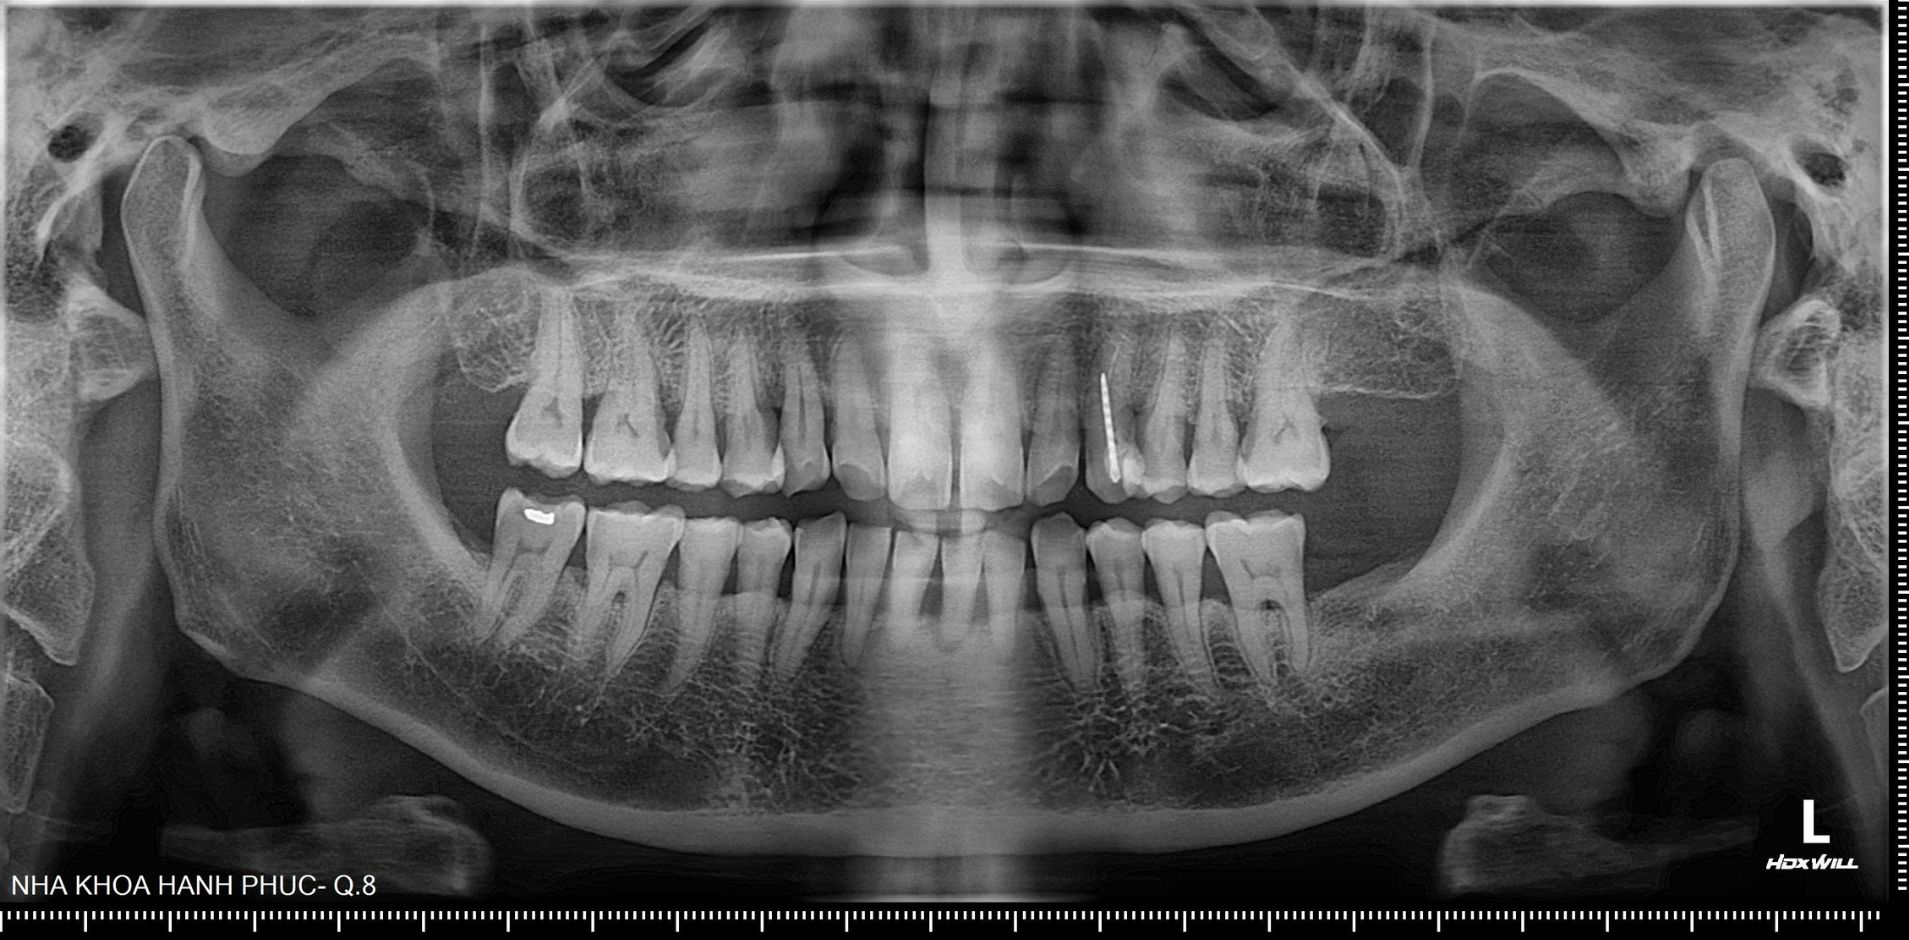

Theo BS.CK1 Phan Bá Ngọc - Giám đốc Phòng khám Nha khoa Hạnh Phúc, bệnh nhân đến khám trong tình trạng đau, răng cửa lung lay độ 3-4. Qua thăm khám và chụp X-quang, bác sĩ phát hiện tình trạng viêm nha chu nặng, tiêu xương ổ răng nhiều, túi nha chu sâu ở 3 răng cửa hàm dưới (R31, R32, R41).

Trước diễn tiến này, bác sĩ chỉ định nhổ 3 răng bị viêm nha chu nặng, sau đó tiến hành cắm 2 trụ implant và làm cầu răng sứ 3 răng. Chi phí điều trị khoảng 39 triệu đồng, trong khi chi phí cạo vôi răng định kỳ chỉ khoảng 200.000 đồng.